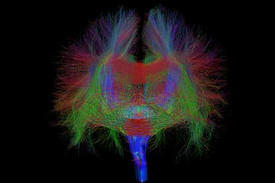

Bei bestimmten Bewegungsstörungen, die nicht oder nicht mehr ausreichend auf eine medikamentöse Therapie ansprechen, ist es möglich, die hierfür verantwortlichen Hirnareale durch die sog. Tiefe Hirnstimulation zu beeinflussen. Hierbei werden feine Elektroden in das Gehirn eingesetzt, um fehlerhafte Nervenstrukturen mit elektrischen Impulsen zu aktivieren oder zu hemmen. Beim Morbus Parkinson, dem essentiellen Tremor oder der Dystonie sind beispielsweise spezifische Hirnareale überaktiv, die dann gezielt durch die Tiefe Hirnstimulation gehemmt und die Symptome wie Zittern oder Muskelsteifigkeit dadurch unterdrückt werden können. Die Hirnregionen selbst bleiben dabei intakt, sodass die Stimulation jederzeit rückgängig gemacht werden kann. Die elektrische Stimulation wird durch einen Impulsgeber gesteuert, der ähnlich wie ein Herzschrittmacher unter die Haut an der Brust der Patient:innen implantiert wird. Die Einstellungen des Impulsgebers lassen sich von außen jederzeit verstellen, sodass die Stimulation an veränderte Bedürfnisse der Patient:innen stets angepasst werden kann.

Neben den Bewegungsstörungen sind mittlerweile auch einige neuropsychiatrische Erkrankungen, wie die Depression oder Zwangsstörungen bekannt, bei denen fehlerhafte Hirnareale durch die Tiefe Hirnstimulation verändert (=moduliert) werden können. Bei schweren therapieresistenten Verläufen kann auch hier dieses Verfahren angeboten werden.